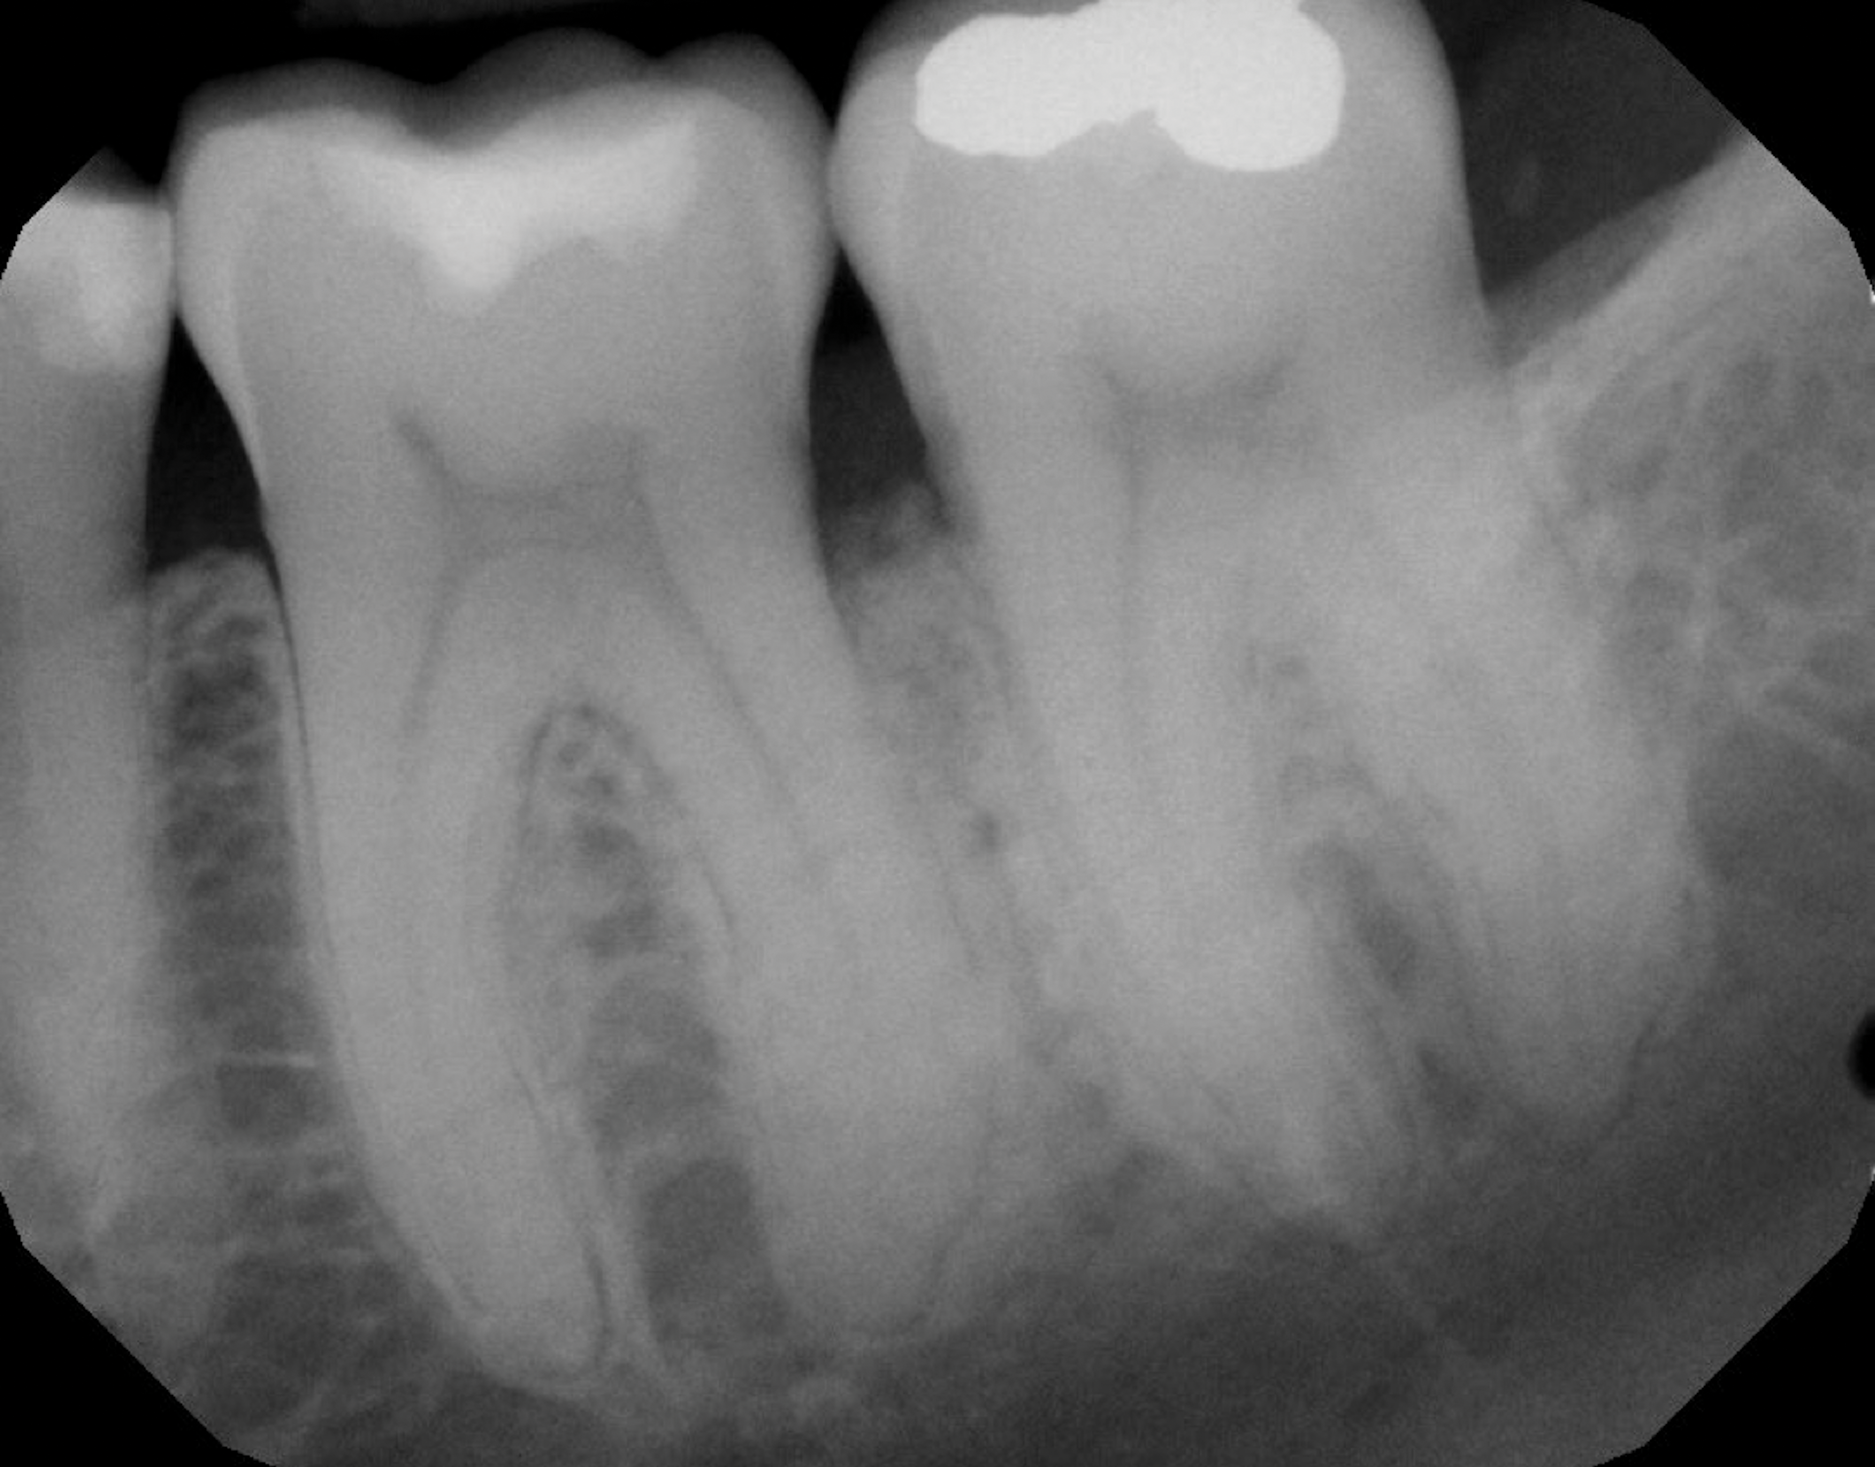

In the present case, the patient's postoperative protocol included the administration of analgesics and mouthrinse. Plaque control and polishing were performed every 2 to 3 weeks for the first 3 months. The patient was then placed on a 3-month recall system. At the 1-year follow-up, stability of the soft and hard tissues could be observed (Figure 13 and Figure 14). Following the seven-key checklist, this clinical case demonstrated that correct case selection, with consideration given to patient-, tooth-, defect-, and operator-related factors, combined with the use of an evidence-based surgical protocol, led to predictable outcomes.

Fig 14. Periapical radiograph revealing healed bone at 1-year follow-up.

Figure 14